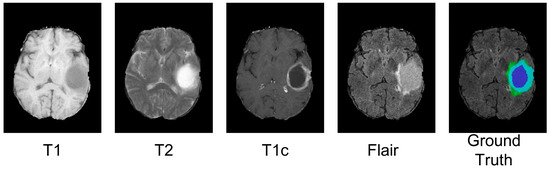

4.3. Analysis of the Bad Tumor Segmentation Results